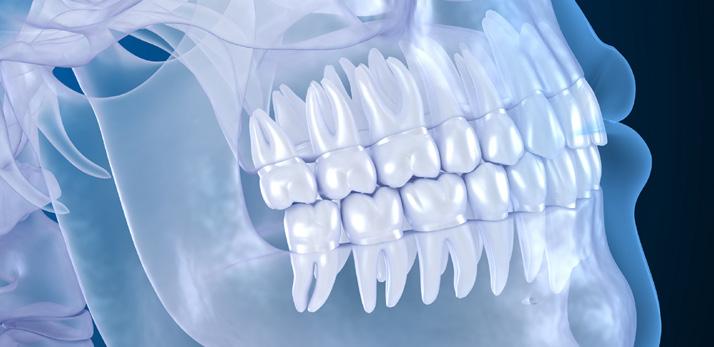

This paper supports the routine use of CBCT as a preoperative decision-making tool for the removal of lower third molars to prevent IAN nerve injuries. The traditional state of the art imaging, orthopantomogram (OPG), may be sufficient in most cases, however CBCT is essential, when one or more signs of close contact between the tooth and mandibular canal are seen on standard panoramic radiography.

This paper presents and highlights the shortcoming of panoramic imaging and elaborates the importance of cone beam CT as an important tool in visualising the course of inferior alveolar nerve in relation to lower third molars. Nowadays the CBCT technology is available in most of the chairside clinics and clinical situation like this can get advantage in achieving proper diagnosis and executing appropriate treatment plan.